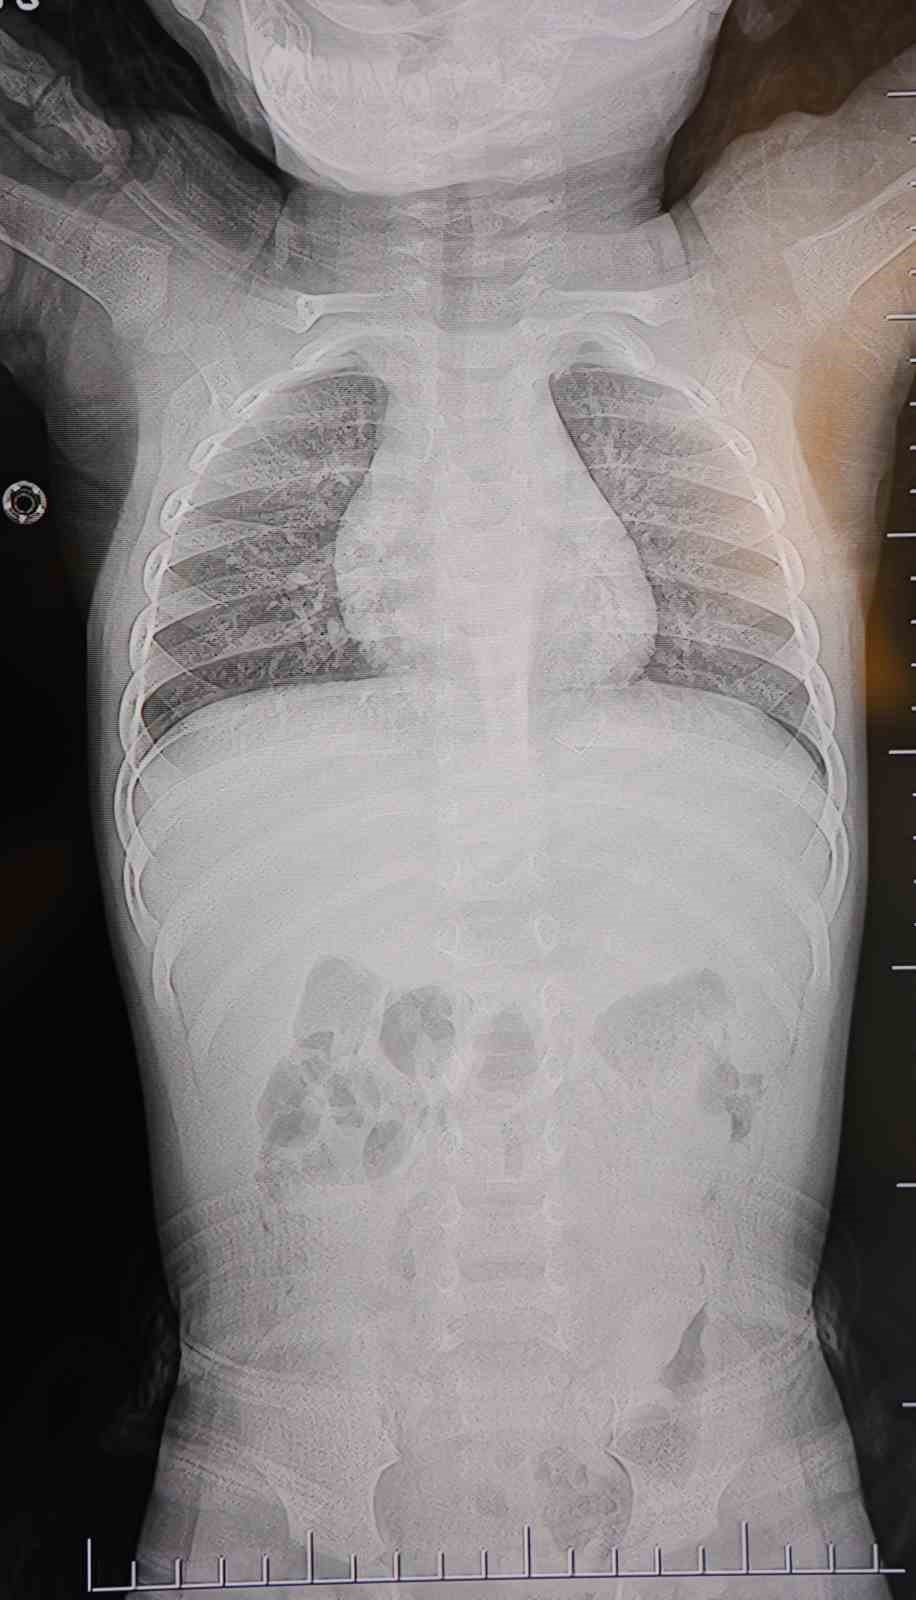

Baba Poyraz, bir gün acil serviste yapılan kontrollerde bebeğin belinde yabancı cisim olduğunu, çekilen filmlerde ise “L” şeklinde zımba teli tespit edildiğini söyledi. Çeşitli hastanelere yönlendirildiklerini anlatan baba, uzun süre müdahale edilmediğini, daha sonra özel bir hastanede yapılan operasyonla zımba telinin çıkarıldığını kaydetti.

Poyraz, bebeğin doğduktan sonra sarılık diyerek kuvöze alındığını belirterek, “Bir hafta orada yattı. Sonra çıkardılar, eve getirdik. Eve geldikten sonra gece gündüz ağlaması hiç durmadı. Tekrar hastaneye götürdüm. Kaşınıyordu, bir hafta banyo yaptıramadık. Sonra duş aldırdım, bağırması daha da arttı. Belini açtık, sırtına baktık, bir şey var mı diye kontrol ettik, görünürde yoktu. Hastaneye götürdük, şurup verdiler. Aylar geçti. Daha sonra acilde bir doktor çocuğumun belinde yabancı cisim olduğunu söyledi. 184’ü aradım, şikayette bulundum. Başhekim yardımcısının yönlendirmesiyle tomografi çekildi. O zaman belinde zımba teli olduğu netleşti. Başka bir hastaneye götürdük, ’riskli, 8 yaşına kadar alınamaz’ dediler, geri gönderdiler. Eve geldikten üç gün sonra oğlum bayıldı. Kardeşimle özel hastaneye götürdük. Orada filmlere baktılar, ’akciğere doğru gidiyor, L şeklinde zımba teli var, alınması lazım’ dediler” dedi.